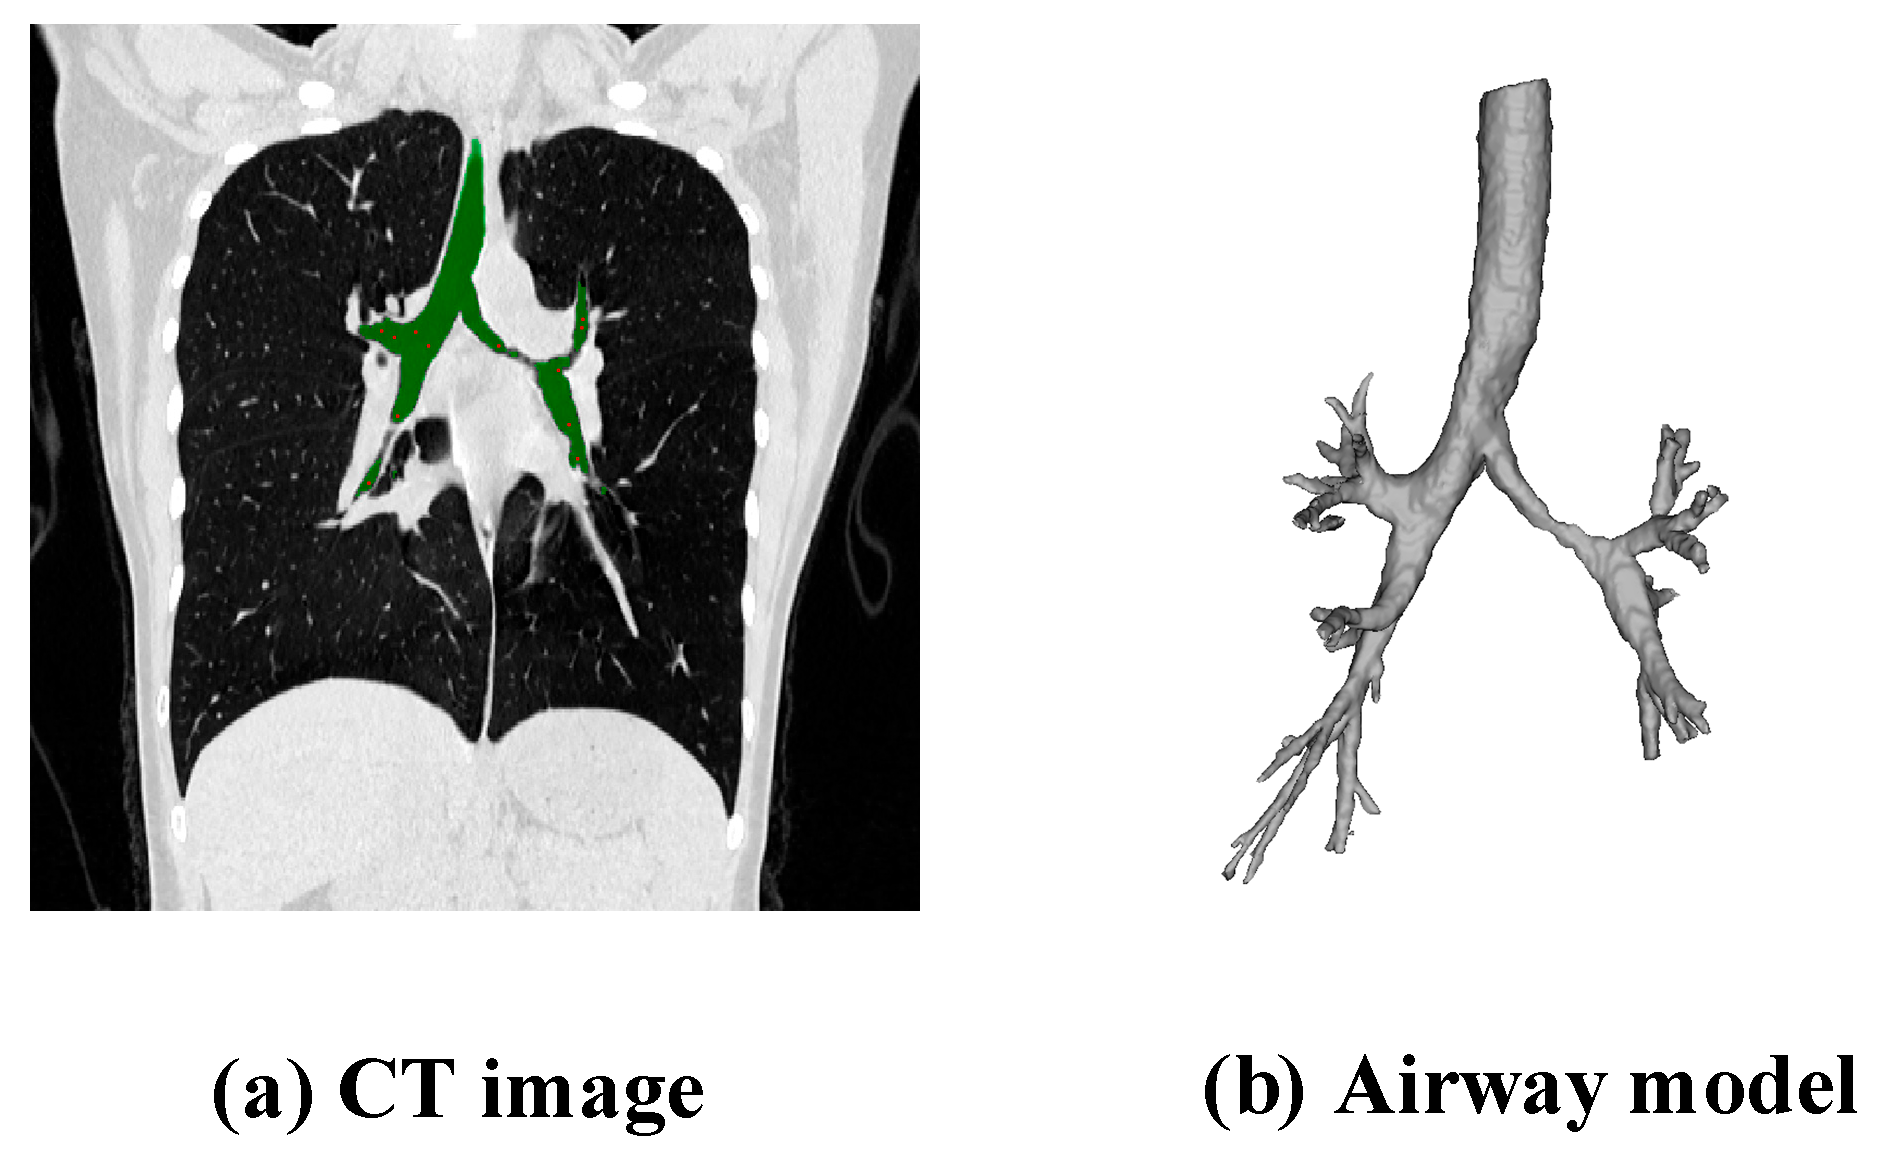

2.2.1. Extraction of Airway Data

2.2.3. Establishment of the Airway Model